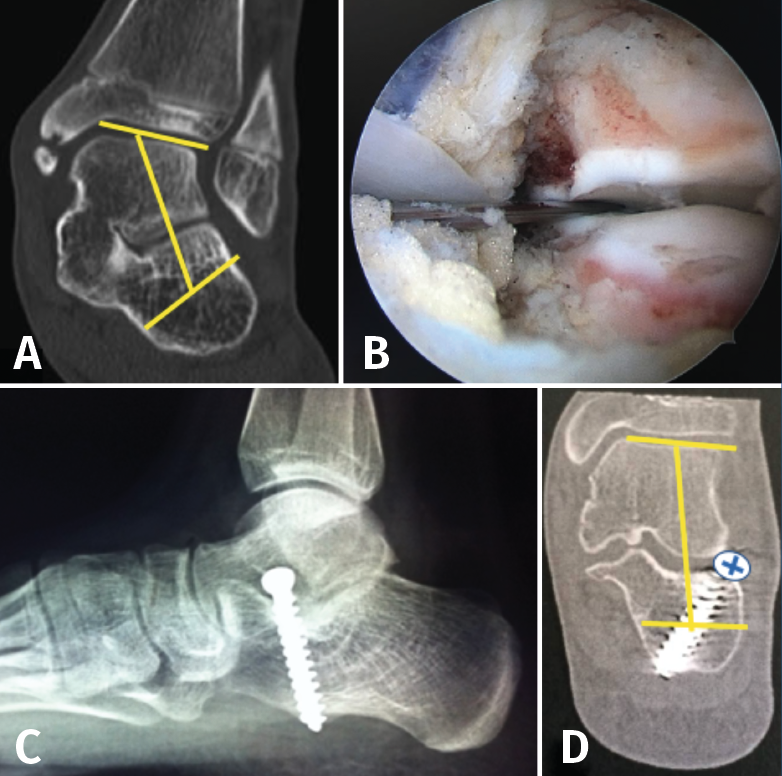

El tratamiento quirúrgico consiste en realizar la exéresis de la coalición de forma abierta con interposición de tejido. El tratamiento moderno consiste en resecar por vía endoscópica la CNC(17) o la TCC(18), sin interposición de tejido. La rápida movilización evita la recidiva. En caso de PPV de más de 20° se puede asociar el tratamiento del calcáneo stop, tras la resección de la coalición(18)(Figura 16).

Figura 16. A: valgo severo de retropié secundario a coalición talocalcánea; B: tras resección completa por vía artroscópica de la coalición, se verifica la movilidad subastragalina, al realizar varo-valgo del talón; C: colocación de calcáneo stop, para corregir el valgo del retropié; D: tomografía axial computarizada de control, donde se visualiza resección de la coalición y corrección del valgo del retropié.

En el caso de PPV secundarios a TCC irresecables, se puede realizar una osteotomía de alargamiento del calcáneo (columna externa)(8).

Como última opción, en sinostosis irresecables y/o con signos radiológicos de degeneración articular, se puede plantear realizar artrodesis subastragalina o una triple artrodesis.